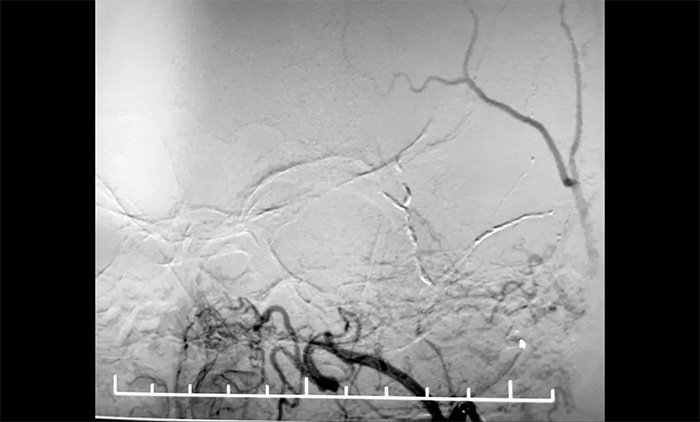

12月29日,順利進(jìn)行手術(shù)。術(shù)中,王貴平博士在介入團(tuán)隊(duì)協(xié)助下克服血管迂曲的困難,導(dǎo)管精準(zhǔn)到達(dá)左腦膜中動(dòng)脈前支、左腦膜中動(dòng)脈后支,之后緩慢注入液體栓塞劑,栓塞劑逐漸向腦膜中動(dòng)脈主干反流,復(fù)查造影,左腦膜中動(dòng)脈無明顯前向血流,手術(shù)成功。術(shù)后,患者無新發(fā)神經(jīng)功能缺損。言語不清,肢體活動(dòng)不利,頭暈等癥狀逐步好轉(zhuǎn)。

▲ 順利栓塞腦膜中動(dòng)脈